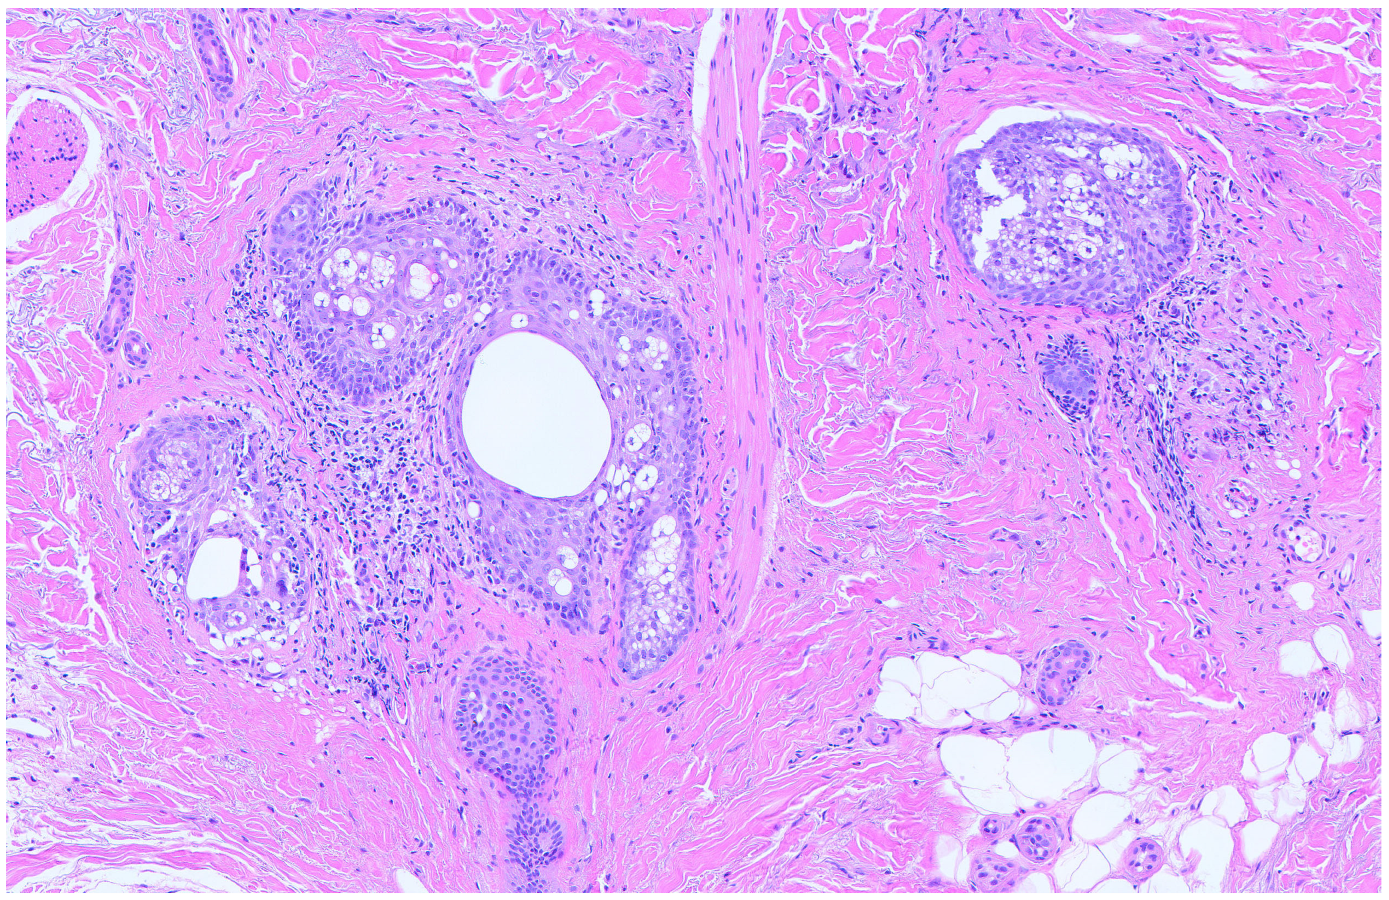

2. Case Presentation